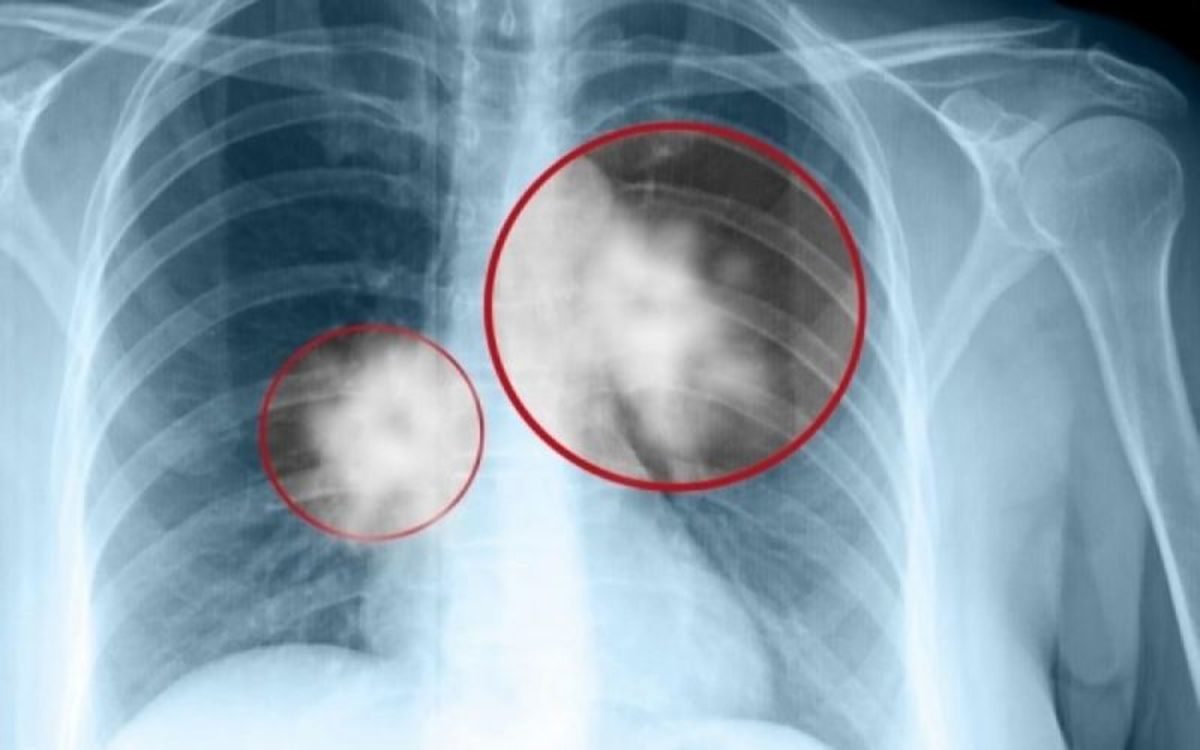

Κατά τα άλλα, τι περιμένατε; Το ακούσαμε από τα πλέον έγκυρα χείλη ότι το 85% των ασθενών με καρκίνο του πνεύμονα ήταν ή είναι καπνιστές. Και κάποιοι από τους υπόλοιπους που ανήκουν στο 15%, ήταν επί σειρά ετών παθητικοί καπνιστές. Για τους υπόλοιπους, αναζητούνται «ένοχα» γονίδια που «προς το παρόν», όπως επισήμανε ο κ. Συρίγος, δεν μπορούμε να αλλάξουμε…

Πάντως, το προσδόκιμο επιβίωσης όσων πετυχαίνουν διάγνωση σε πρώιμα στάδια καρκίνου του πνεύμονα, κάνουν χειρουργική επέμβαση και θεραπεία και συνεχίζουν την ζωή τους κανονικά… Και στους υπόλοιπους, με πιο προχωρημένα και επιθετικά είδη καρκίνου του πνεύμονα, υπάρχουν πολλά να γίνουν και ζουν πια αρκετά χρόνια… Γενικά έχει περάσει πια η εποχή που ο συγκεκριμένος καρκίνος οδηγούσε αμέσως στο θάνατο.

Παρόλα αυτά, όπως μας είπε ο καθηγητής, είναι σημαντικό τα άτομα της ομάδας υψηλού κινδύνου (καπνιστές) να οδηγούνται αμέσως στο πνευμονολόγο αν χειροτερέψει ο βήχας τους, έχουν δύσπνοια, ή έχουν πτύελα με αίμα ή νιώσουν πόσο στη μέση και το στήθος… Όσο πιο γρήγορα γίνει η διάγνωσή τους, τόσο πιο σίγουρο είναι ότι θα ιαθούν.